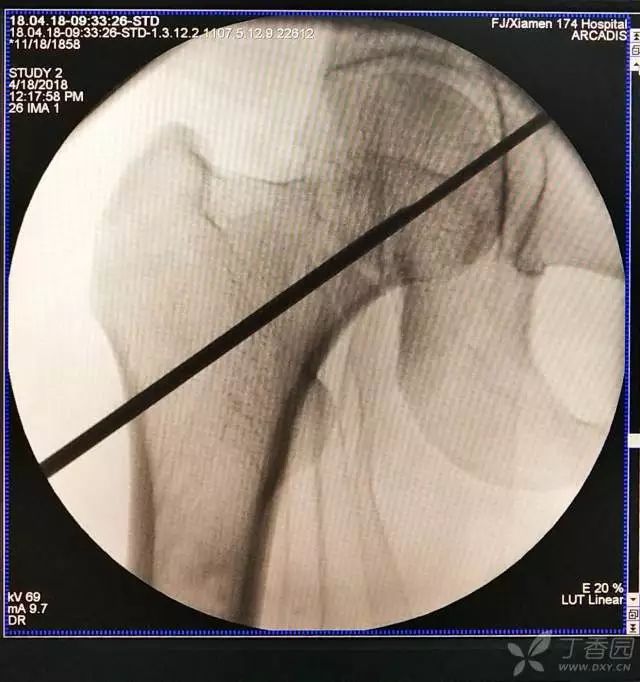

3. 再努力一把就基本成了